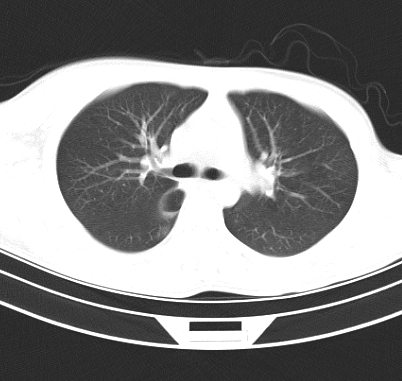

标题: CT19170:男 24岁,胸部外伤一周行CT检查 [打印本页]

男 24岁,胸部外伤一周行ct检查 未传纵隔窗

考虑右肺下叶纵隔胸膜下液气囊肿。

考虑外伤肺撕裂致右肺下叶纵隔胸膜下液气囊肿。

结合临床考虑为右肺下叶背段撕裂伤后形成局限性包裹性的液气胸。

首先考虑肺裂伤形成的液气囊肿.纵膈胸膜包裹性的液气胸可能性小,病变主要在肺内.